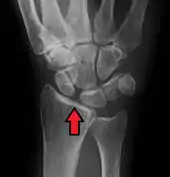

Dynamic scapholunate instability visible upon clenching the wrist

X-ray images indicate scapholunate ligament instability when the scapholunate distance is more than 3 mm, which is called scapholunate dissociation.[7] A static scapholunate instability is generally readily visible, but a dynamic scapholunate instability can only be seen radiographically in certain wrist positions or under certain loading conditions, such as when clenching the wrist, or loading the wrist in ulnar deviation.[6]

In order to diagnose a SLAC wrist you need a posterior anterior (PA) view X-ray, a lateral view X-ray and a fist view X-ray.[8] The fist X-ray is often made if there is no convincing Terry Thomas sign. A fist X-ray of a scapholunate ligament rupture will show a descending capitate bone. Making a fist will give pressure at the capitate, which will descend if there is a rupture in the scapholunate ligament.